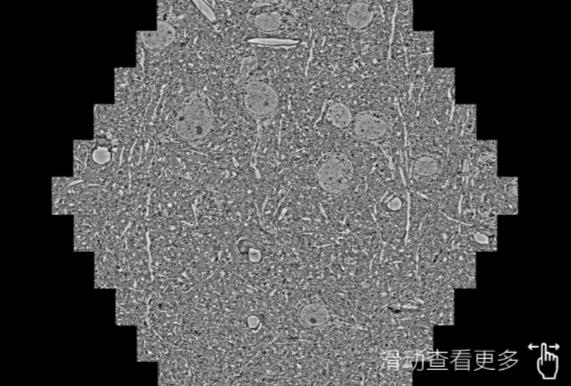

鼠脑切片。左图使用达州蔡司达州扫描电镜MultiSEM706对165μmx143pm面积区域成像,耗时仅需1.5秒。右图为鼠脑切片中30μm区域放大效果。样品由芝加哥大学B.Kasthuri提供。

使用蔡司高速达州扫描电镜MultiSEM对1mm²人脑皮层组织进行高分辨成像,并对其中的各种细胞结构进行三维重构分析。左图展示了2x3mm²组织平面中锥体神经元的三维重构效果。右图显示了局部体积神经元三维重构。图像由哈佛大学chtman实验室提供,渲染图由D. Berger 制作。